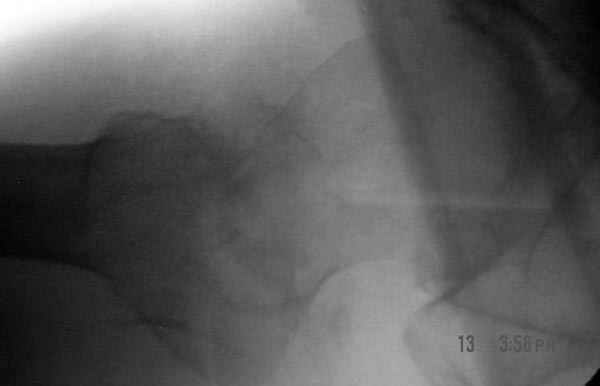

Второй случай тоже репозиция из малого доступа, больному 19 лет, множественные огнестрельные повреждениия конечностей, живота и черепа, правая конечность холодная, без пульсации. Ортопедический диагноз: огнестрельный перелом правого бедра. При срочной ангиографии повреждения сосудов не подтвердилось, конечность из-за ургентности состояния больного зафиксирована временным наружным фиксатором и больной оставлен на операционном столе для срочной лапаротомии хирургической службой.

Больной долго оставался нестабильным, только на 14 день удалось заменить на антеградный интромедуллярный штифт TFN (trochanteric femoral nail) SmithNephew. После неудачной попытки закрытой репозиции, несмотря на использование "joystick", проксимальный стержень от

наружного фиксатора, (перелом начал срастаться) репозицию провели из малого доступа, затем остальные этапы операции.

Случай был представлен из-за того, что больного оперировали после наружной фиксации и был риск инфекцирования через места проведения стержней (на снимках), прошло больше 3 месяцев, выписан из амбулаторной службы из-за отсутсвия надобности дальнейшего наблюдения.